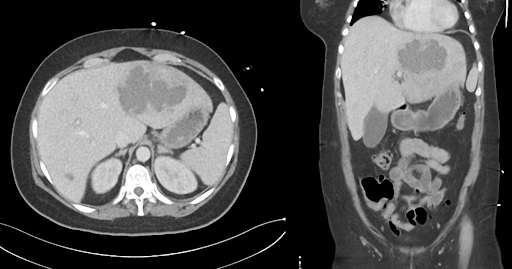

CT-Abdomen mit Kontrastmittel:

CT-Abdomen mit Kontrastmittel

Amöbischer Leberabszess durch Entamoeba histolytica, vermutlich erworben während des NGO-Einsatzes in Bangladesch.

Ein bakterieller Leberabszess ist differenzialdiagnostisch naheliegend, jedoch sprechen mehrere Befunde gegen diese Diagnose: Die Patientin hatte keinen bekannten biliären Infekt, keinen intraabdominellen Fokus wie eine Appendizitis oder Divertikulitis und keine kürzliche Sepsis. Zudem ist die Reiseanamnese mit Aufenthalt in einem Endemiegebiet deutlich suggestiver für einen amöbischen Ursprung.

Eine Hydatidenzyste (Echinokokkose) ist eine weitere wichtige Differenzialdiagnose bei zystischen Leberläsionen, insbesondere mit Auslandsaufenthalt. Im vorliegenden Fall ist die Läsion jedoch nicht zystisch mit multiseptierter Struktur, sondern nekrotisch und solide-inflammatorisch. Zudem fehlen spezifische Serologien und die typische kalzifizierte Kapsel, die für eine Echinokokkenzyste sprechen würden.

Insgesamt ist die Kombination aus epidemiologischer Anamnese, Klinik, Bildgebung und positiver Serologie die Diagnose eines amöbischen Leberabszesses am wahrscheinlichsten.